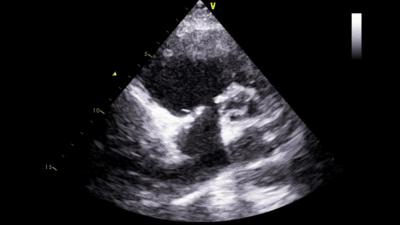

2月26日,终于等到手术的日子。由于患者是二次开胸,我院心脏中心团队格外谨慎谨慎,全力以赴。术中发现,患者胸部切口和胸骨都有感染,心脏周围粘连非常紧密,仅是开胸和分离心脏周围粘连就用了2个多小时。为患者建立体外循环,打开心脏探查三尖瓣时发现:三尖瓣隔叶仅为残迹,后叶缺如,前叶面积也只有正常一半,而且没有腱索和乳头肌牵拉。发生这样的病变,只有换瓣才能挽救患者的生命。可是三尖瓣瓣环已经被人工成形环固定,心内膜已经把成形环包埋起来,需要先拆掉成形环。但真是说起来容易,做起来难啊。三尖瓣瓣环比较薄,周围还有右冠状动脉和房室结。如果不谨慎撕坏三尖瓣瓣环,损伤冠状动脉或损伤房室结,都会造成严重并发症。吴清玉教授沉着冷静,凭着丰富的手术经验,顺利地拆除了成形环,置换好新的人工瓣膜。患者心脏复跳,手术堪称完美。由于术前准备充分,术中节血措施完备,整个手术仅使用红细胞4个单位,患者术后12天就顺利康复出院了。